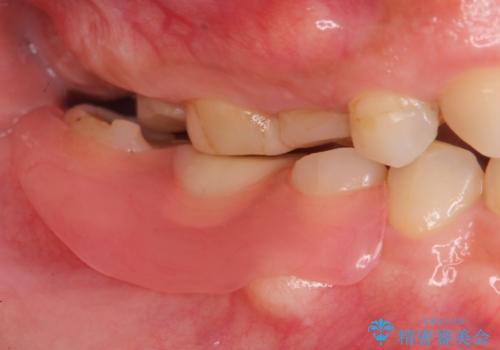

- 欠損し、放置していた奥歯に審美性に優れる入れ歯を作製したいと希望され来院されました。

ノンクラスプデンチャーは、入れ歯に通常ついている目立つ銀色のバネがないため審美性に優れる入れ歯です。

ノンクラスプデンチャーは、ブリッジのように隣りの歯を削る必要もなく、インプラントのように手術も必要ない方法です。